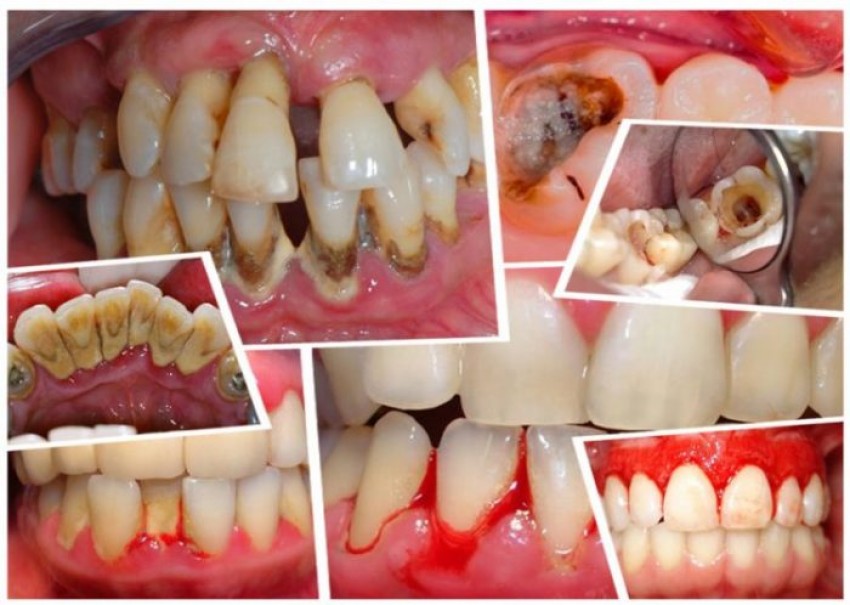

Cao răng là một chất lắng cặn cứng của các muối vô cơ gồm canxi carbonat và phosphate phối hợp với cặn mềm (mảnh vụn thức ăn, các chất khoáng trong môi trường miệng), vi khuẩn, xác các tế bào biểu mô, sự lắng đọng sắt của huyết thanh, bám rất chắc vào bề mặt răng hoặc dưới bờ lợi (còn gọi là vôi răng). Cao răng có hai loại: cao răng thường và cao răng huyết thanh. Cao răng thường như đã mô tả ở trên. Khi cao răng thường gây viêm lợi, lợi ở vùng viêm sẽ tiết dịch viêm và chảy máu, máu ngấm vào cao răng thường tạo nên màu nâu đỏ, lúc này mảng cao răng đó được gọi là cao răng huyết thanh.

Cao răng có thể dẫn đến các bệnh như viêm lợi với các biểu hiện đánh răng chảy máu, miệng có mùi hôi. Cao răng cũng có thể gây viêm nha chu dẫn đến tiêu xương làm răng bị đau, ê buốt khi ăn uống, nặng hơn có thể gây lung lay và rụng răng. Ngoài ra, cao răng còn gây viêm tủy ngược dòng. Vi khuẩn trong mảng cao răng cũng là một trong những nguyên nhân gây các bệnh ở niêm mạc miệng (viêm niêm mạc miệng, áp-tơ mà dân gian vẫn gọi là bệnh lở miệng), bệnh ở vùng mũi họng (viêm amidan, viêm họng), bệnh tim mạch.

Có nhiều lý do để phải lấy cao răng thường xuyên. Trong đó phải kể đến độc tố của vi khuẩn trong mảng cao răng gây ra viêm. Từ phản ứng viêm này gây ra hiện tượng tiêu xương ở răng làm cho lợi mất chỗ bám dẫn đến càng ngày răng càng dài, để lộ ra vùng xương răng không được tổ chức quanh răng bảo vệ. Bệnh nhân sẽ thấy xuất hiện cảm giác ê buốt khó chịu.